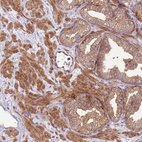

Immunohistochemical staining of human testis shows strong cytoplasmic positivity in cells in seminiferous ducts.